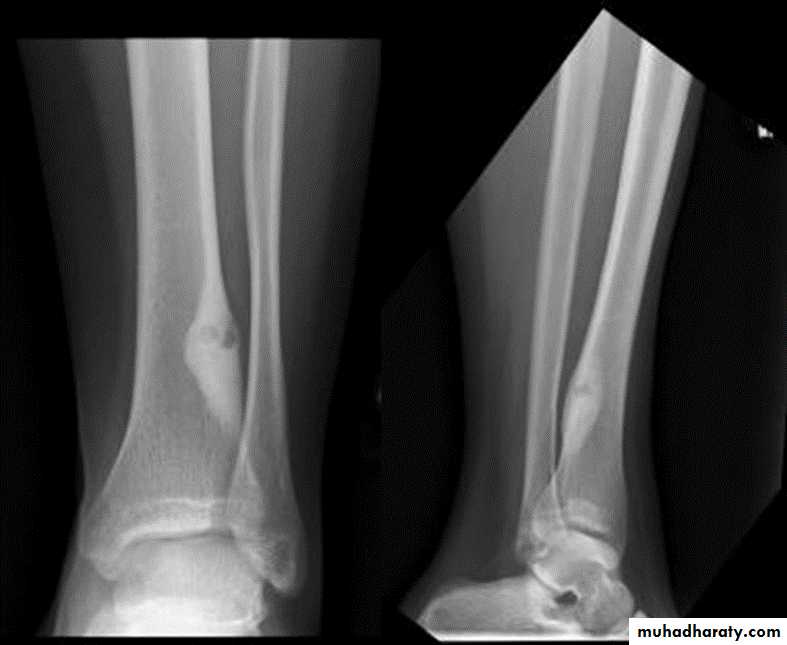

Solitary bone cyst:

Age: young adults & children.Site: long bones.

Findings: well-defined expanding lytic lesion.

A piece of cortical bone has broken off and descended through the serous fluid contained within the lesion and can be seen in the dependent portion of the lesion (arrow) as

a fallen fragment sign.

A fallen fragment sign is said to be pathgnomonic for

a unicameral bone cyst

Fallen fragment sign